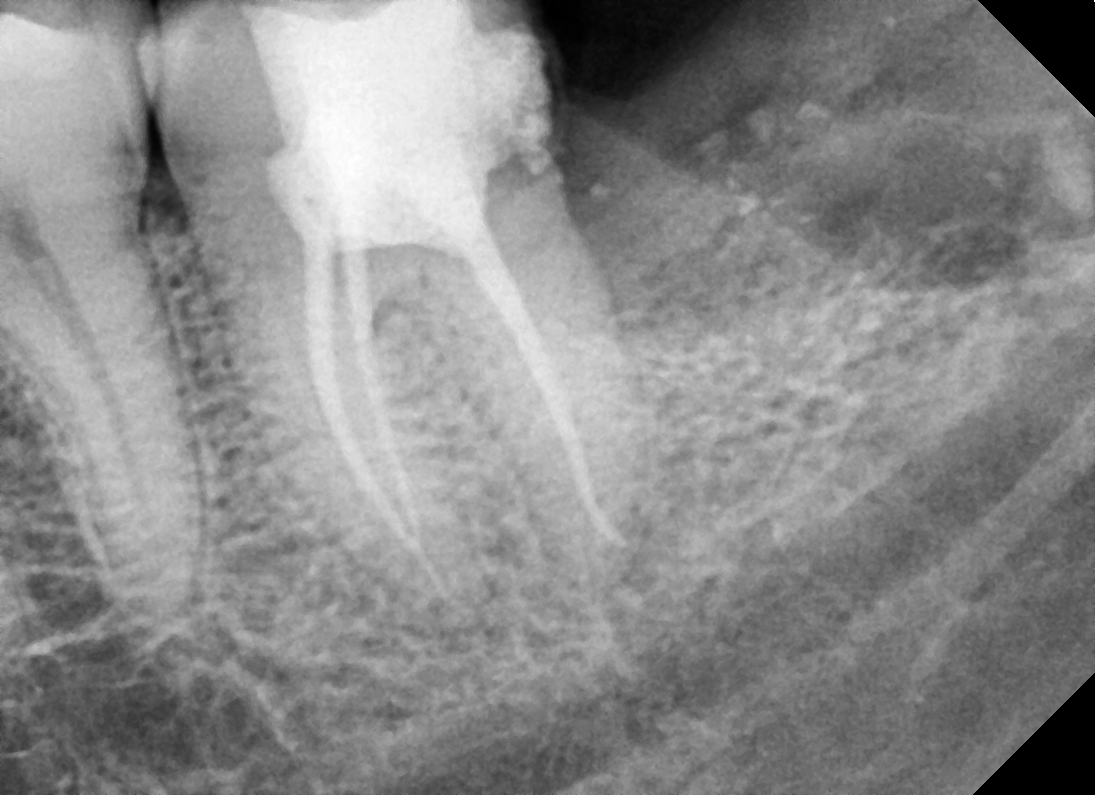

Disto Angular

After After

Before Before